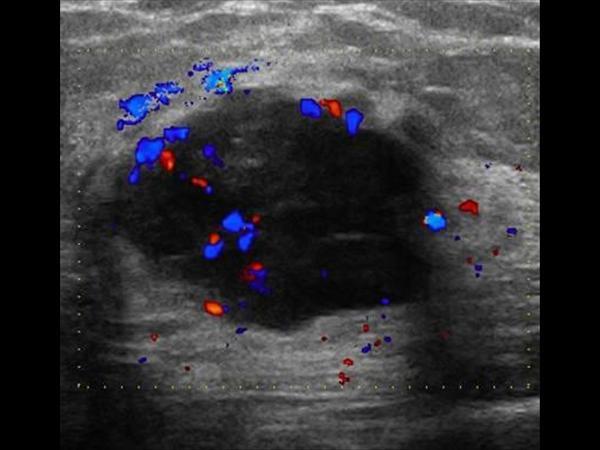

Why are neither color or power Doppler reliable in distinguishing benign from malignant lesions?

both may demonstrate internal flow

Why is Doppler helpful during a breast exam?

distinguishing

solid vs cystic - flow confirms a solid

inflamed vs noninflamed - increased flow

complex cyst vs intraductal papilloma

True or False?

Doppler can positively confirm solid vs cystic lesions

False

flow confirms a solid

flow does NOT confirm cystic

Color Doppler - more peripheral and internal flow